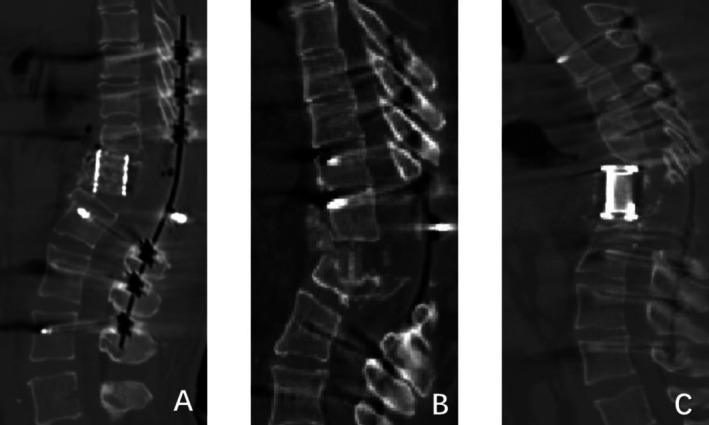

目的:大量研究报道了颈腰椎退行性疾病患者椎间融合器(IFDs)匹配不良的表现及影响因素。然而,目前还没有研究解决在后路脊柱切除术(PVCR)手术中使用ifd匹配的问题。本回顾性影像学研究的目的是分析PVCR后ifd匹配不良的相关危险因素。方法:回顾了2006年6月至2024年7月期间92例PVCR后使用ifd的患者的数据。将ifd植入失败、相邻椎体骨折、沉降大于5mm、角度形成超过10°、错位(定义为超过匹配界面外缘的ifd的三分之一)作为筛选指标,将患者分为匹配不良组和匹配组。通过单因素和多因素logistic回归分析评估匹配不良的潜在危险因素。以受试者工作特征曲线下面积(AUC)评价多元回归模型。结果:92例患者中37例(40.2%)匹配不良。单因素logistic回归分析显示,术前、术后矢状Cobb角、截骨面夹角、置入椎体总数、切除椎体数、ifd高度、钛网或人工椎体的使用是导致匹配不良的潜在危险因素。多因素逐步回归分析显示,术前矢状Cobb角(OR = 1.053, p = 0.001)、截骨面夹角(OR = 1.152, p = 0.003)、ifd高度(OR = 1.058, p = 0.033)是吻合不良的独立危险因素。对于匹配差的情况,该多元回归模型的总体预测性能(AUC = 0.872)令人满意。结论:在PVCR中使用ifd与高的即时匹配不良率相关。术前矢状Cobb角、截骨面夹角、ifd高度是吻合不良的独立危险因素。

Methods: Data from 92 patients using IFDs following PVCR between June 2006 and July 2024 were reviewed. IFDs implantation failure, adjacent vertebral fractures, subsidence greater than 5 mm, angle formation exceeding 10°, and malposition (defined as one-third of the IFDs exceeding the outer edge of the matching interface) were used as screening indicators to divide patients into poor matching and matching groups. Potential risk factors of poor matching were assessed through univariate and multivariate logistic regression analysis. The multiple regression model was evaluated by the area under the receiver operating characteristic curve (AUC).

Results: Among the 92 patients, 37 (40.2%) experienced poor matching. Univariate logistic regression analysis revealed that the preoperative and postoperative sagittal Cobb angles, the angle between osteotomy surfaces, total instrumented vertebrae, the number of vertebrae resected, the height of IFDs, and the use of titanium mesh or artificial vertebral bodies were potential risk factors for poor matching. Backward stepwise multivariate logistic regression analysis indicated that the preoperative sagittal Cobb angle (OR = 1.053, p = 0.001), the angle between osteotomy surfaces (OR = 1.152, p = 0.003), and the height of IFDs (OR = 1.058, p = 0.033) were independent risk factors for poor matching. The overall predictive performance of this multiple regression model (AUC = 0.872) for poor matching was deemed satisfactory.

Conclusion: The use of IFDs in PVCR was associated with a high rate of immediate poor matching. The preoperative sagittal Cobb angle, the angle between osteotomy surfaces, and the height of IFDs are independent risk factors for poor matching.